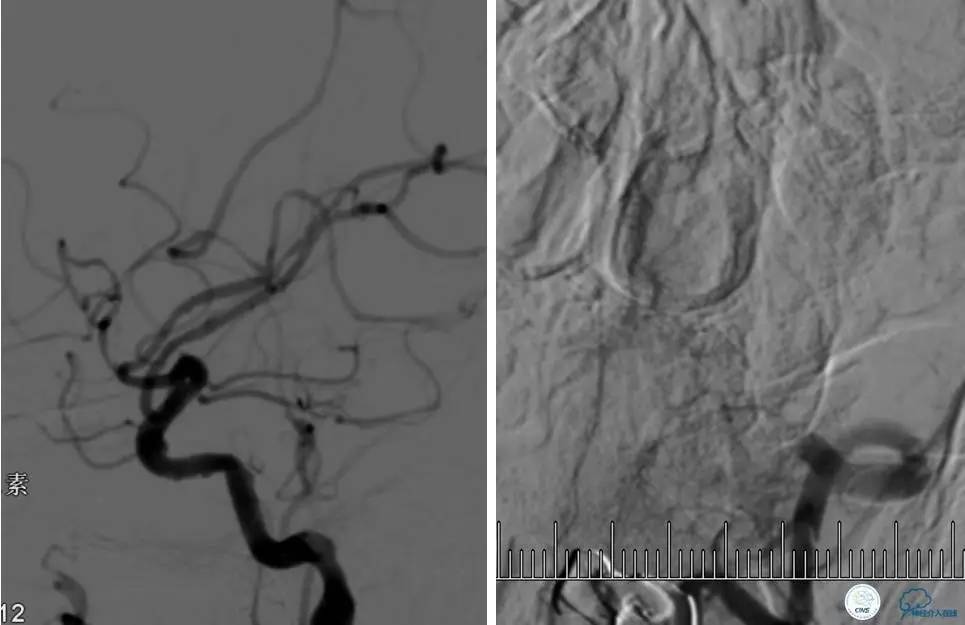

病例7

患者:反复发作右侧肢体无力、言语不清15天。

导丝很容易通过闭塞段。

顺利置入Wingspan支架,成功开通,手术顺利。